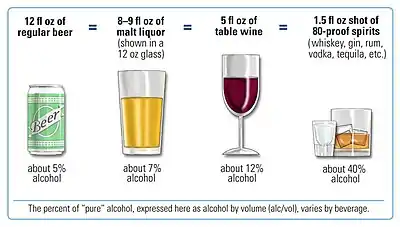

- modifiable risk factors (things that people can change themselves, such as consumption of alcoholic beverages), and

Drinking alcoholic beverages increases the risk of breast cancer, even among very light drinkers (women drinking less than half of one alcoholic drink per day).[50] The risk is highest among heavy drinkers.[52] Globally, about one in 10 cases of breast cancer is caused by women drinking alcoholic beverages.[52] Drinking alcoholic beverages is among the most common modifiable risk factors.[53]